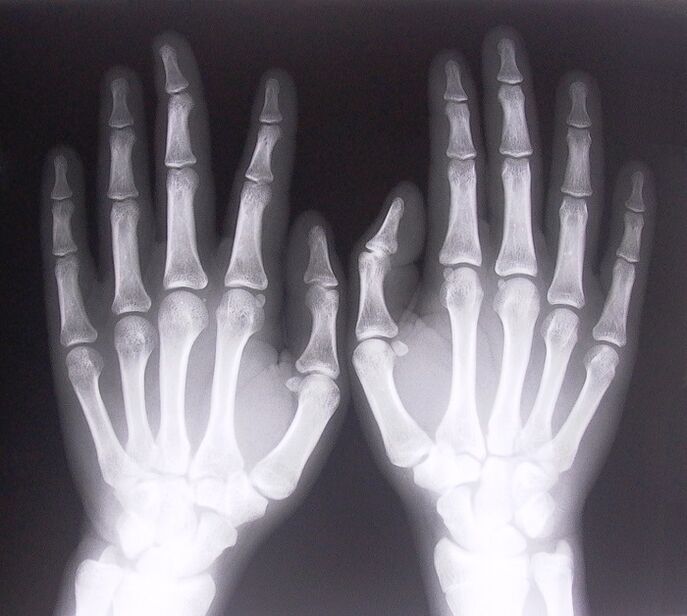

- Ligamentitis stenosis. Untuk mengetahui penyebab penyakitnya, perlu dilakukan pemeriksaan rontgen. Gejalanya khas: gerakan tangan nyeri, telapak tangan terkepal. Selain itu, selama ekstensi, biasanya terdengar bunyi klik.

Untuk mulai mengobati nyeri sendi pada jari, Anda perlu menentukan dengan benar penyakit apa yang menyebabkannya. Untuk mengetahui jenis penyakit apa yang menimpa seseorang yang merasakan nyeri pada persendian saat menekuk lengan, dokter menyarankan untuk menjalani prosedur berikut ini:

- Ambil rontgen.